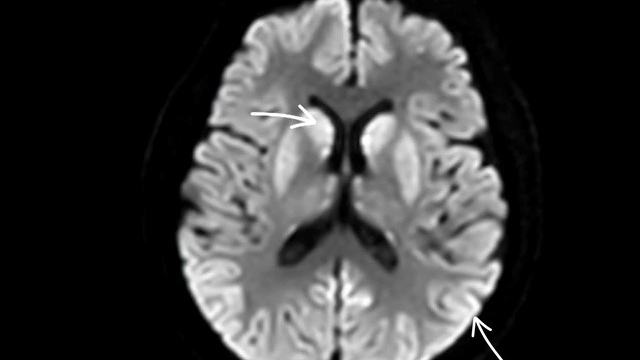

![]() |

| Bác sĩ phẫu thuật cho bệnh nhi (Ảnh: Bệnh viện cung cấp) |